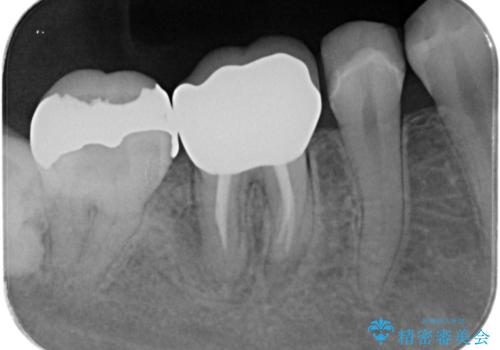

歯茎が腫れた。ジルコニアクラウンやりかえ。

歯茎が腫れたとの事で歯の神経が失活していたので精密根管治療を行い、ジルコニアクラウンで治療を行いました。

- ジルコニアクラウンスタンダード・仮歯 12.1万円 精密根管治療(イニシャルトリートメント)・ファイバーコア 13.2万円費用は治療当時の料金となります